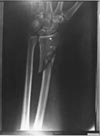

President Kennedy wasn't the only victim in the Dallas motorcade on 22 Nov 1963. Governor Connally, riding in the "jump seat" ahead of Kennedy, was also shot. His wounds included an entry wound in the back near the right shoulder, a broken rib, an exit wound in the chest, a shattered wrist caused by a bullet entering from the dorsal (back) side, and a fragment lodged in his thigh.

Among the many problems with the single bullet theory and Connally's wounds in particular, there is also the issue of whether the metal fragments taken from Connally's wrist and left in his leg could possibly have come from the nearly intact bullet CE 399. JFK autopsy surgeon Commander Humes told the Commission "I can't conceive of where they came from this missile." There is also some doubt about whether the fragments now in evidence (CE 842) comprise all that was removed from Governor Connally's wrist.